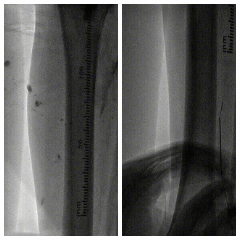

图:推送saber球囊

图:开通腘动脉主干

图:4mm/5mm球囊顺序行股腘动脉PTA,3mm球囊行腓动脉PTA

图:由肱动脉先行股动脉支架置入,而后顺行穿刺股总动脉

图:胫腓干夹层,置入3.5mm*35mm药涂支架(冠脉支架)

图:术后造影示股腘动脉、腓动脉及足部动脉显影好